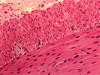

skeletal muscle

skeletal muscle

skeletal muscle

skeletal muscle

skeletal muscle

skeletal muscle

what tissue is this from?